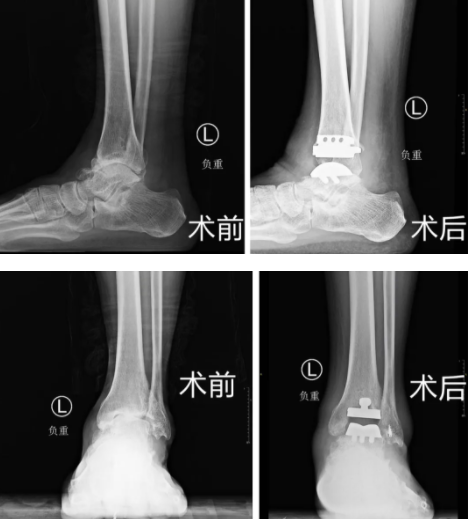

十多年前,赵大叔左脚崴了一次,疼了很久,但一直没有正规治疗过,也就敷敷膏药,休息几天,慢慢的踝关节状况越来越差,最后拖成了终末期踝关节炎。当时来院的时候赵大叔脚部情况很差,距骨坏死,外侧副韧带有陈旧的疤痕,踝关节的周围都是骨赘,而且软骨的损伤是比较重的,踝关节正常的关节面已经不存在了,每走一步都疼痛不已。

对于终末期踝关节炎,临床治疗有两种方法,一是关节融合,就是将关节固定,患者踝关节不能再曲伸,二是全踝关节置换,可以保留踝关节功能。经过沟通,大叔选择了可以保留踝关节活动的全踝关节置换术。

这次家访的时候,赵大叔通过锻炼已经具备了踝关节正常跖曲和背伸的功能,曹广超主任通过查体发现小腿肌肉力量仍有不足,后续还要通过锻炼来加强小腿肌肉的力量。

人工踝关节置换术是近年来临床一项新技术,目前只在国内一些大城市医院开展。betway在线登陆2022年底引进此项技术,术前根据患者踝关节三维CT数据,运用数字骨科技术,设计并打印个体化截骨导板,术中应用截骨导板进行定位、截骨,减少了术中X线透视次数,缩短了手术时间,保证稳定性,极大提高了手术精准度和成功率。